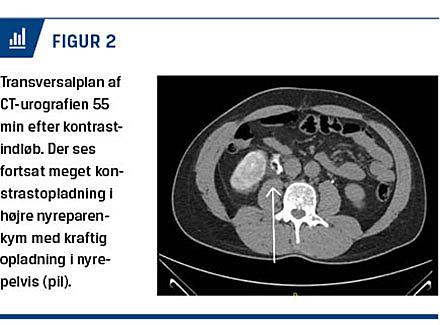

Ved en CT uden kontrast af abdomen blev der på venstre side fundet et konkrement, som var 4 mm i diameter, i en øvre calyx uden hydronefrose. På højre side var der udtalt stranding og lidt væske omkring højre nyrepelvis samt let hydronefrose (Figur 1). Der var ingen sten i højre nyre eller i højre ureter, og urinblæren var tom. På baggrund af ovenstående blev der fundet indikation for CT-urografi på mistanke om fornixruptur. CT-urografien viste væskeansamling proksimalt omkring højre nyrepol.